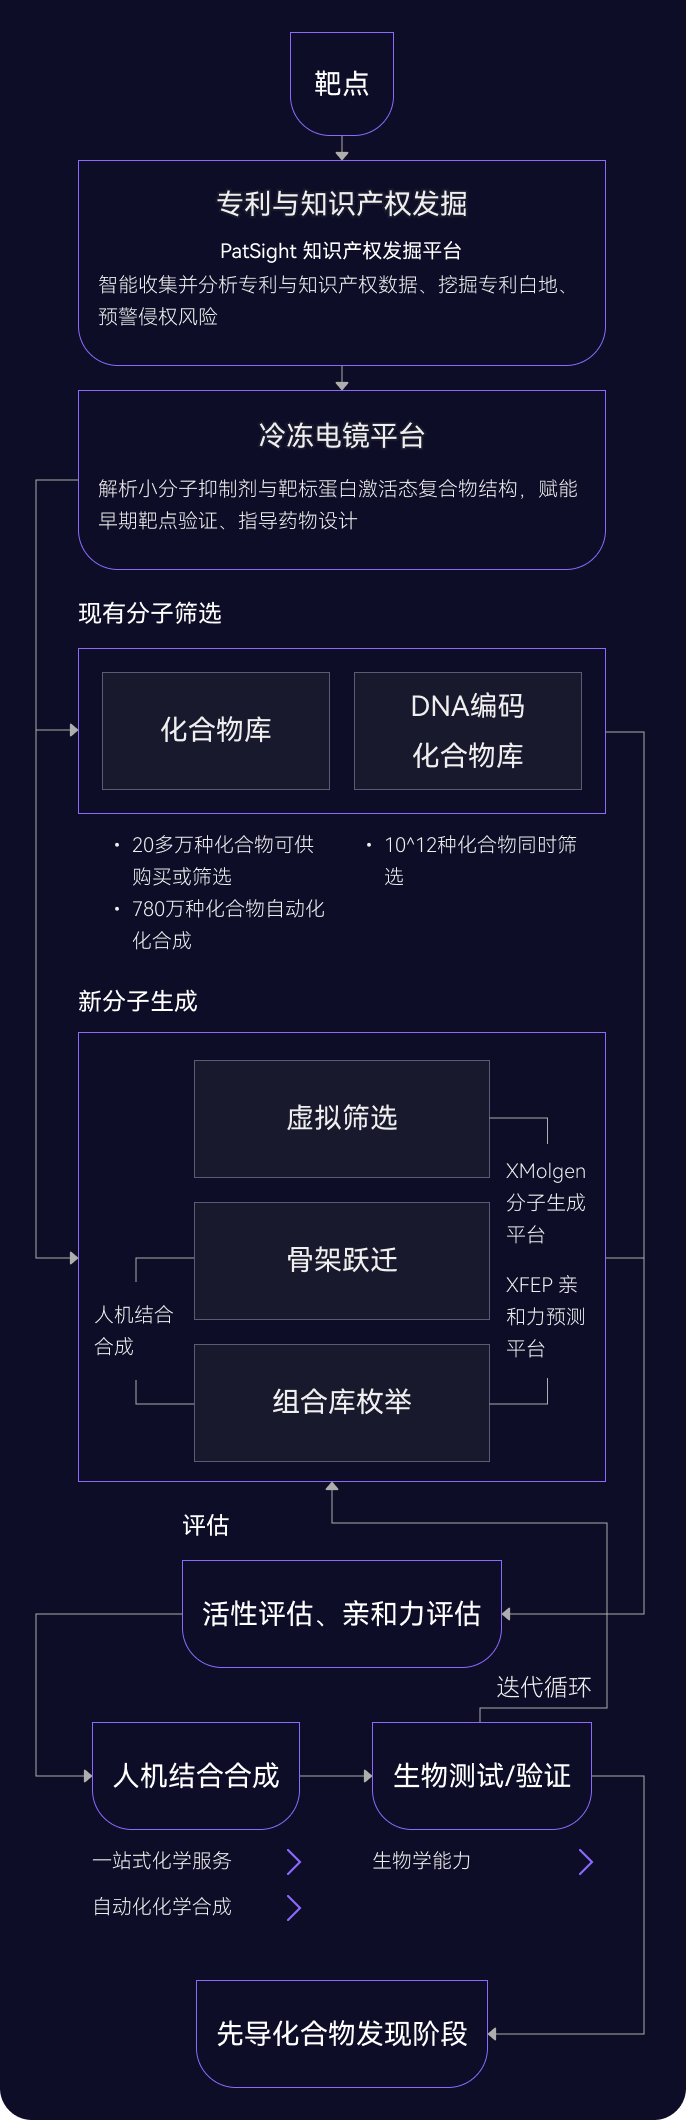

03 藥物發現平臺

ID4Inno 藥物發現平臺

04 苗頭化合物階段

多管齊下

發現最佳苗頭化合物

AI 擴展化學空間

基于AI與物理模型的有機結合,更快、更準確地探索更廣闊的化學空間,開啟您的藥物發現之旅

- 骨架躍遷和組合庫枚舉

- 200萬個分子砌塊,將化學空間擴展到1012化合物庫

- 成功為95%的項目發現苗頭化合物 (60個項目中有57個已完成)

高效藥物篩選

通過全方位的篩選,精準鎖定最具潛力的臨床前候選化合物

- 20多萬種類藥化合物可供購買或內部篩選

- 超過780萬種化合物可通過自動化化學合成

- AI驅動的自動化平臺,實現高效的篩選和數據分析

DNA編碼化合物庫

通過廣泛的多樣性和精準篩選加速發現過程

- 可同時篩選數十億種化合物,增加發現新穎苗頭化合物的機會

- 僅需少量的目標蛋白就可進行測試開發,使早期藥物發現高效且易于實施

05 先導化合物階段

尋找最佳先導化合物

并優化成藥性質

先導化合物評估與優化

通過優化活性、選擇性和類藥性,將苗頭化合物轉化為先導化合物

- 利用生成式AI(XMolGen)進行分子和庫設計,增加骨架新穎性和化合物多樣性

- 通過先進的物理計算(XFEP)進行虛擬篩選,優化活性和類藥性

- 通過專有自動化平臺,實現快速且可靠的中間體和庫合成

自動化助力先導化合物優化

在進入臨床前試驗前,優化先導化合物提高療效和安全性,改善藥代動力學特性。

- 借助自動化濕實驗室化學能力,快速而穩健進行SAR分析,指導化合物設計

- 內部動物實驗室支持體內研究,包括藥代動力學/藥效學(PK/PD)、療效、安全性、劑量和代謝,推進臨床前開發

- 先進的力場技術,準確計算自由能微擾,預測結合親和力

AI 驅動的全流程藥物發現

全流程一體化支持

從靶點到臨床前候選全流程藥物的發現一體化解決方案